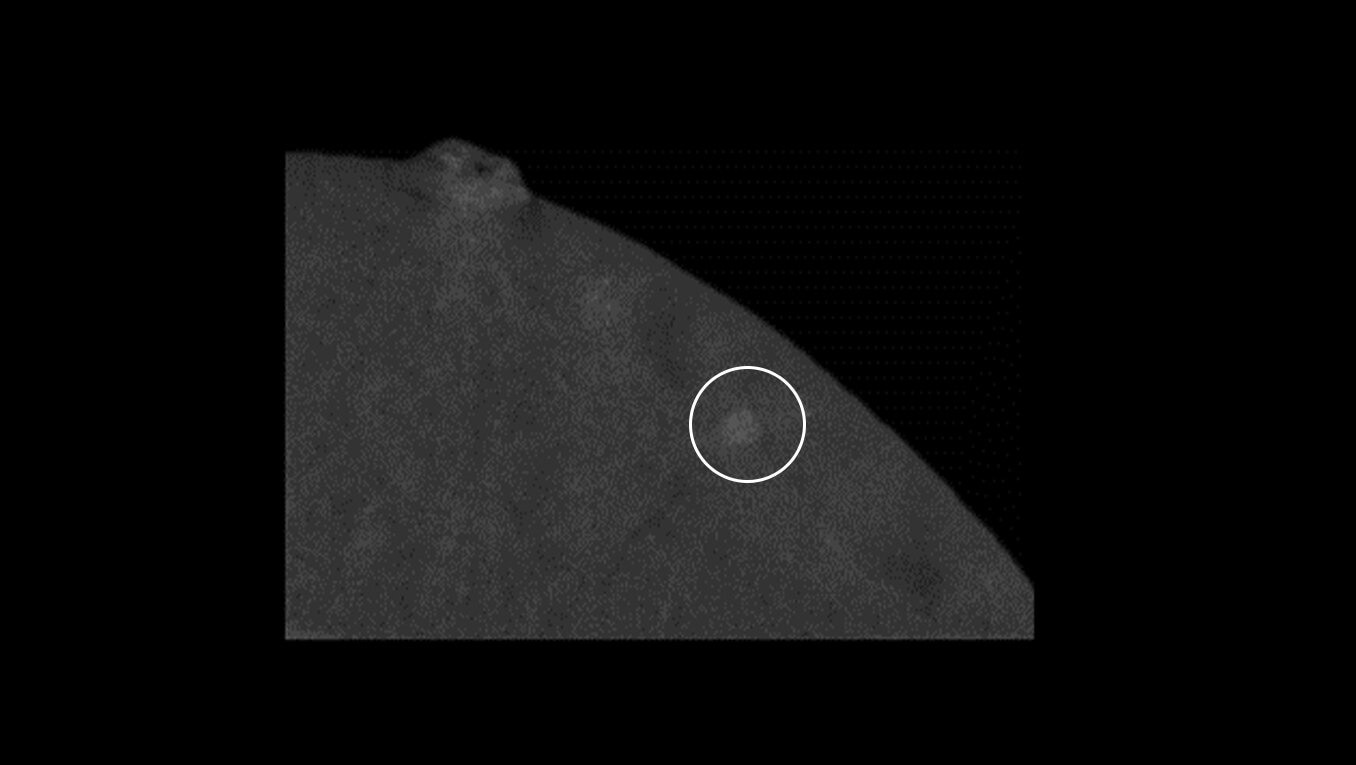

Fast procedure

CEM biopsy can be done within 15 minutes1.

Switch to interventional on the same system within your current room in 2 minutes4.